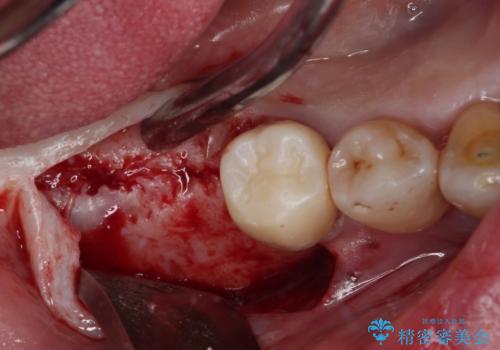

- インプラント治療を前提に下顎の部分矯正を始めたものの、そのまま長い間放置しているとのことで来院された患者様です。

全体的に歯肉が腫れており、歯周病により抜歯をしなければならない歯がある状態でした。

矯正治療を仕上げ、必要に応じて歯周外科処置を行い、適宜インプラントを埋入しながら咬み合わせを回復させていくこととしました。

治療前は磨き残しが多く見られ、全体的に歯肉が腫れている状態でしたが、抜歯の必要な歯を抜いたことで口腔内の環境が改善され、磨き残しも少なくなってきました。